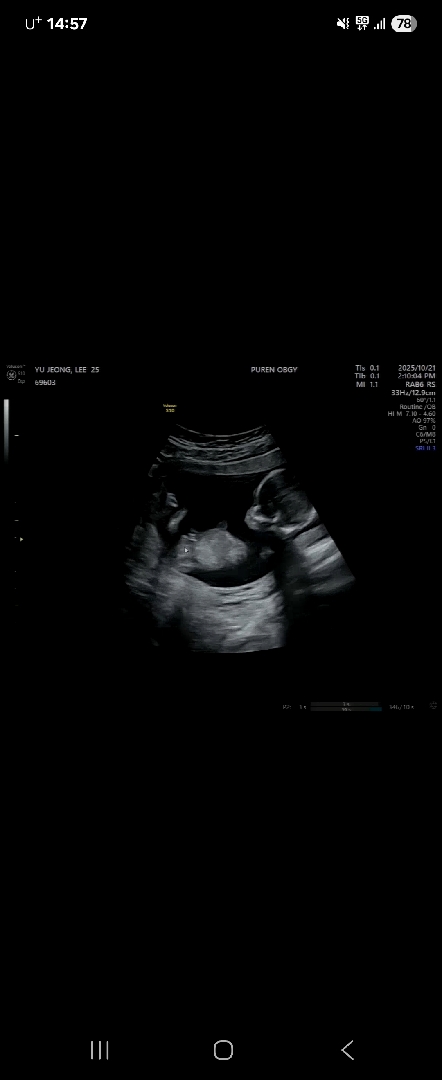

15주차 4일 성별

원장님이 초음파보시더니 아들이네요해서 바뀔확률은 없겠죠? 하니까 아들일확률 300퍼입니다. 이러시는데 저랑 와이프는 초음파에 고추가 어딨다는거지?하는데 15주차라 성별 바뀔확률은 없겠죠..?

저도 어제 15주에 가니 아들확인해주시더라구요! 저는 고추 몇번이나 콕 집어 보여주시던데ㅠㅠ